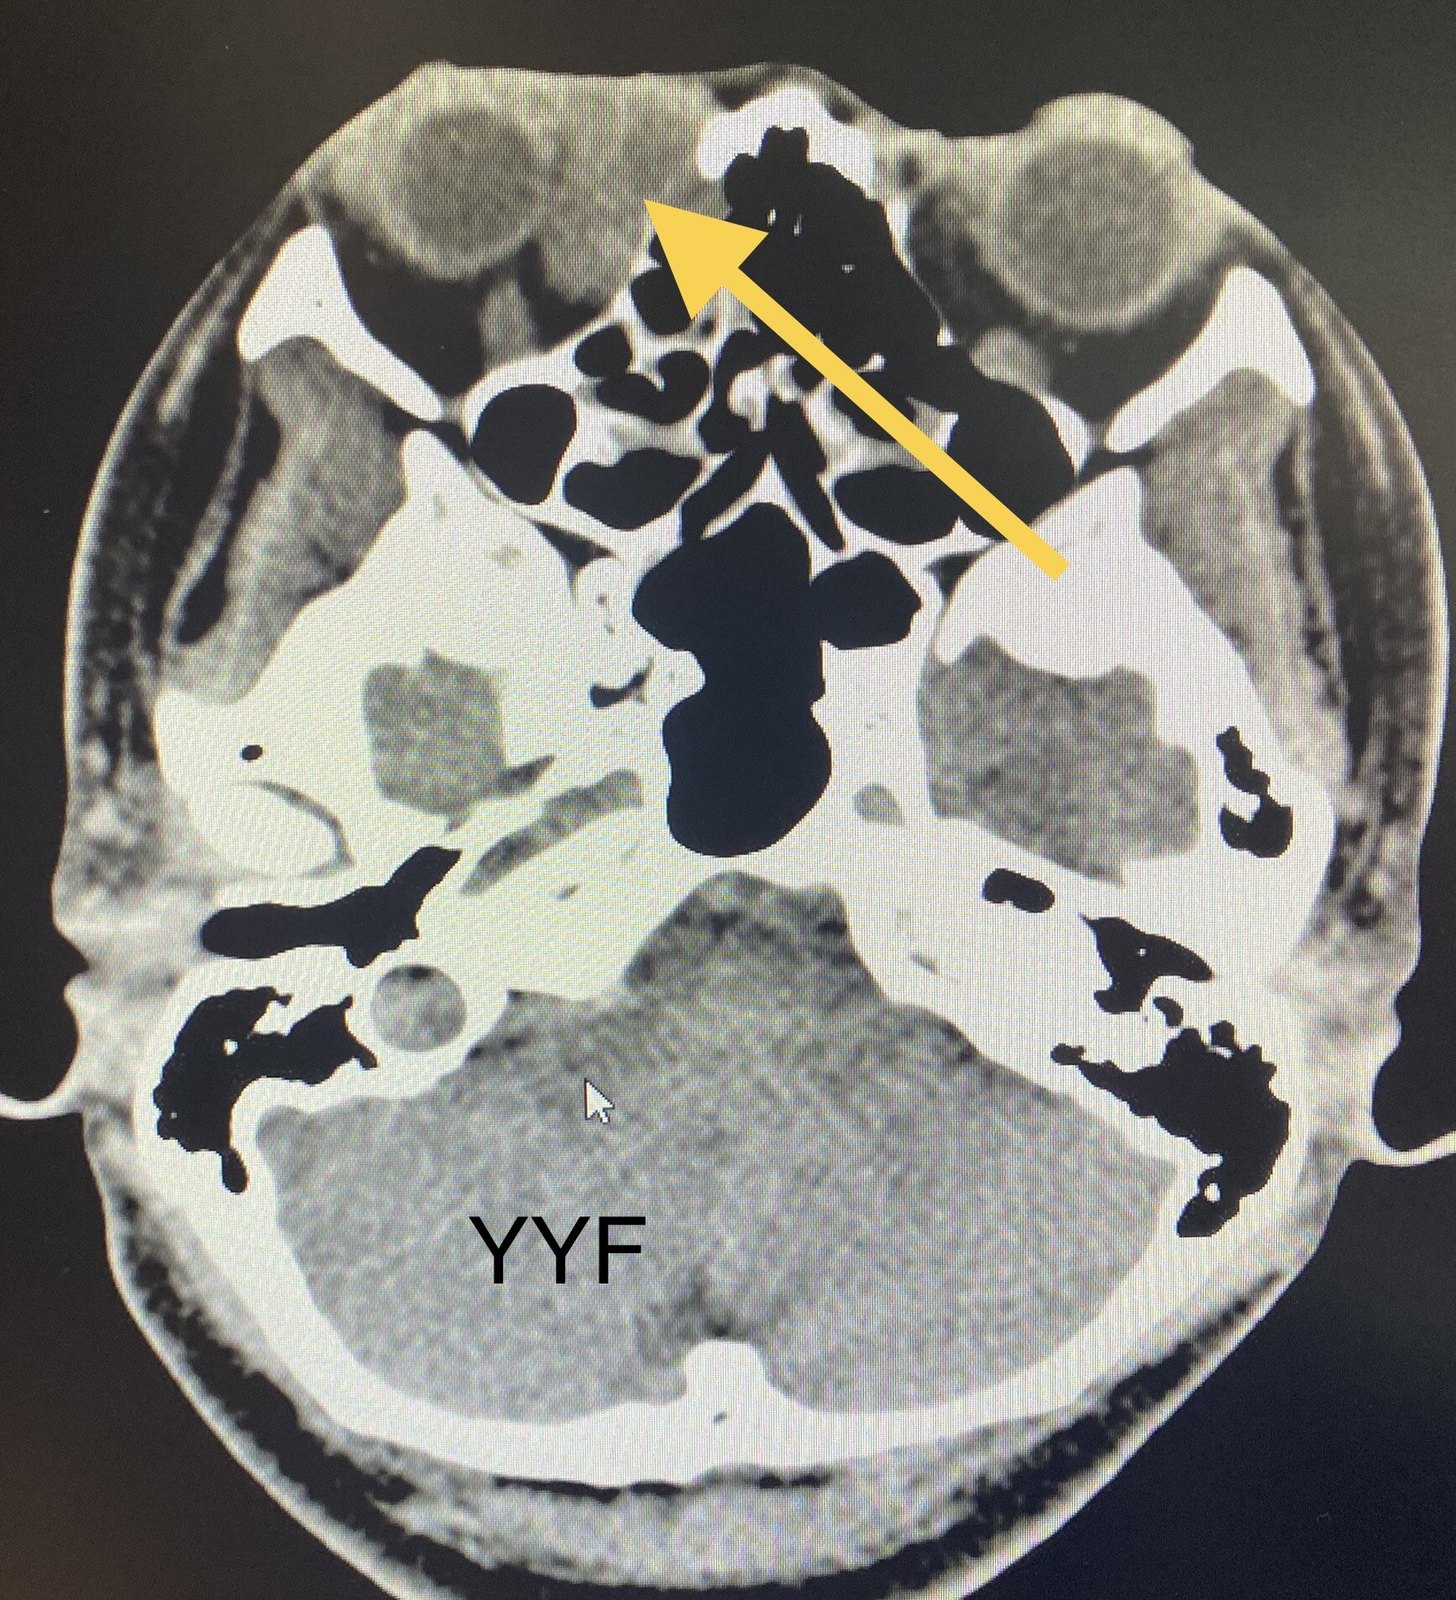

【泪器疾病讨论】早期曾被误诊的泪囊肿瘤 [病例帖]

肿物位于泪囊区,有"炎症"表现,又是女性患者(泪道阻塞性疾病女性更好

ct显示病变以泪囊区为主,但已经超越泪囊仔细分析疾病的发病特点和